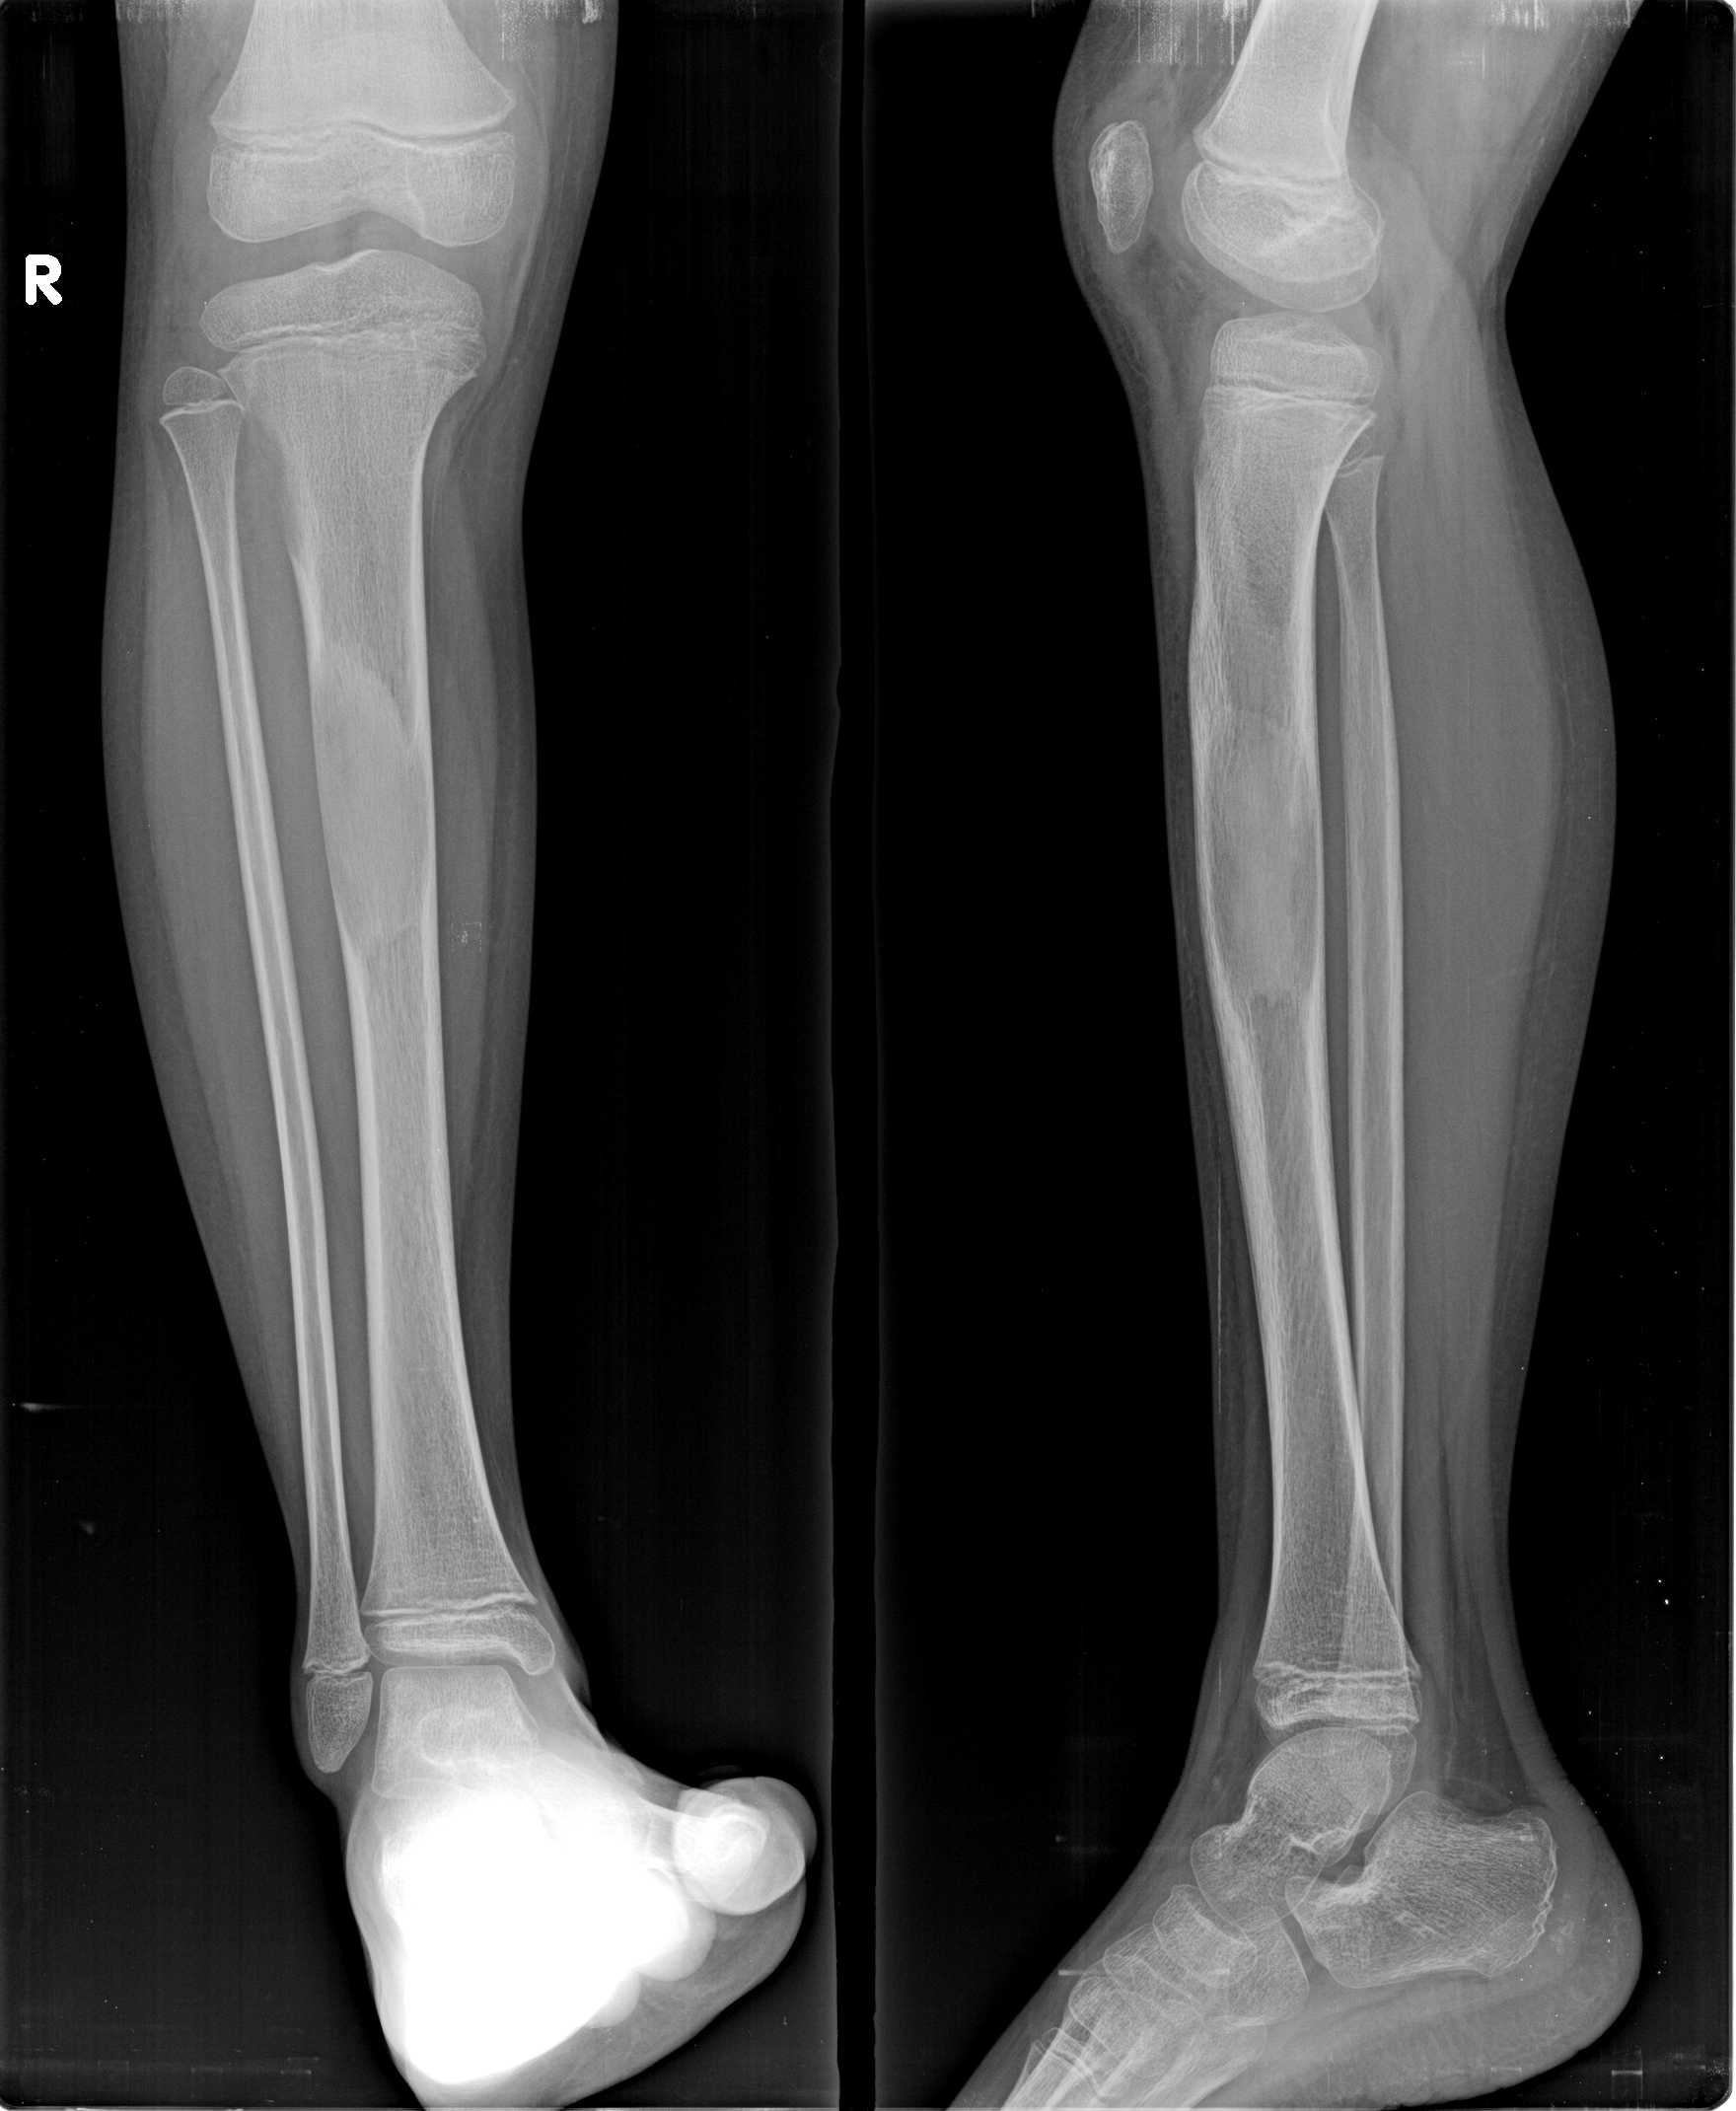

以下是引用zhangzhongshou在2008-5-24 13:32:00的发言:[br]胫骨膨胀性骨质破坏区,骨皮质变薄,内呈磨玻璃状模糊影,符合胫骨骨纤维异常增殖症。

以下是引用dyqct在2008-5-24 16:56:00的发言:[br]磨玻璃状模糊影,符合右胫骨骨纤维异常增殖症。 [br] [br]